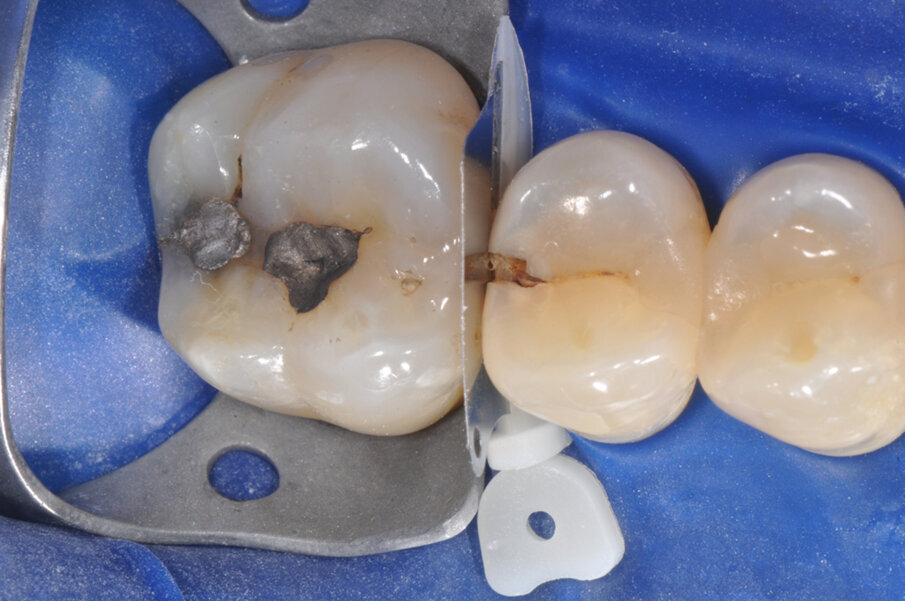

Il caso riguarda l’esecuzione di un restauro interprossimale col sistema di matrici sezionali anelli separatori e cunei Composi-Tight 3D Fusion. Il paziente presenta carie penetrante (D3) a carico dell’elemento 1.5 distale. Viene posizionata la diga di gomma (Fig. 1).

Viene posizionato un cuneo con matrice allo scopo di proteggere il dente aprossimale (Fig. 2). La cavità è stata preparata, la carie asportata, i margini cavitari devono essere rifiniti (Fig. 3). Vengono rimossi il cuneo e la matrice per meglio rifinire il gradino cervicale e per valutare che tipo di cuneo utilizzare (Fig. 4). Ai fini di migliorare l’adattamento della matrice viene utilizzata una striscia abrasiva in plastica di grana media (Fig. 5).